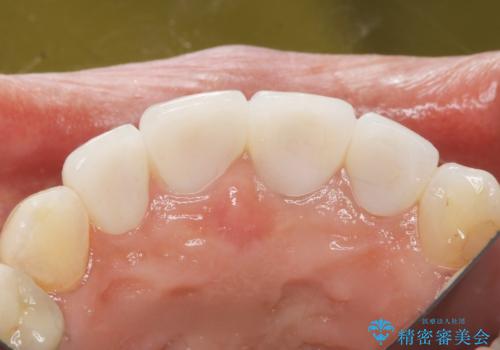

5年前のクラウン装着時と比較したところ、歯肉が成熟し歯間乳頭ができており、より天然歯のように自然に見えました。

患者様の良好なセルフケアと精密な適合の良いクラウンにより、歯肉の腫脹や退縮も認められませんでした。

5年前に行った治療に大変ご満足頂き、他の部位も治療やホワイトニングを希望して下さいました。

人工のダイヤモンドにも用いられるジルコニアは、セラミック系素材の中でも圧倒的に丈夫かつ審美的で、劣化しにくく口腔内でも長期間安定した状態を保つことができます。

クラウンの種類:ジルコニアオールセラミッククラウン スタンダード